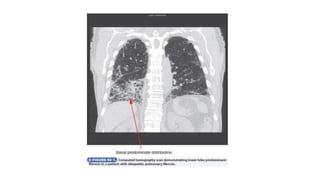

• Nonspecific Interstitial Pneumonia

Diagnosis

• Chest radiographs show bilateral patchy pulmonary infiltrates with a

• HRCT reveals a predominant ground-glass pattern of attenuation,

• In contrast, fibrotic nonspecific interstitial pneumonia has a bilateral

lower lobe distribution with architectural derangement on HRCT;